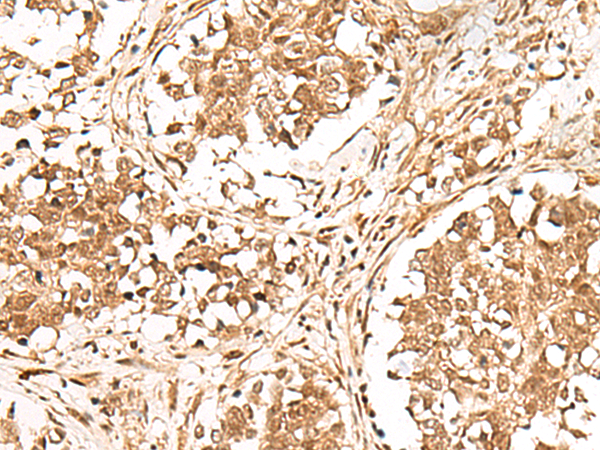

The image is immunohistochemistry of paraffin-embedded Human esophagus cancer tissue using P13471(GMEB2 Antibody) at dilution 1/30. (Original magnification: ×200) |

The image is immunohistochemistry of paraffin-embedded Human lung cancer tissue using P13471(GMEB2 Antibody) at dilution 1/30. (Original magnification: ×200) |